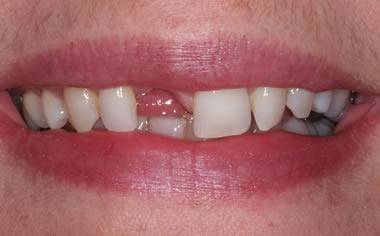

Before & After Gallery

More front teeth replaced by dental implants

Case Four (6 images)